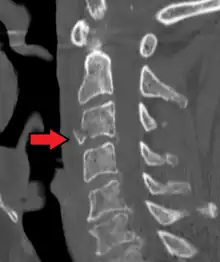

| A fracture of the base of the dens (a part of C2) as seen on CT. | |